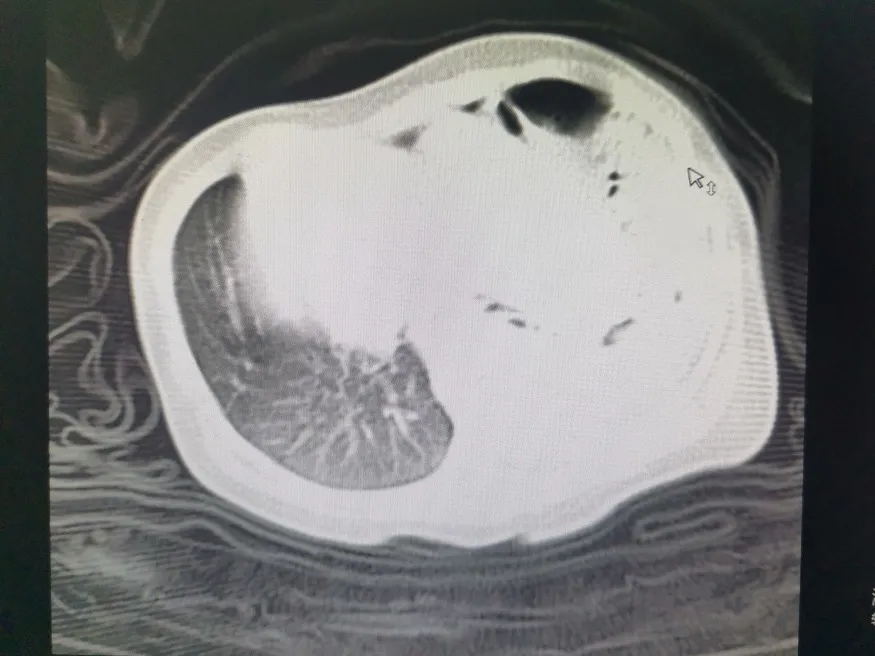

术前CT

据悉,韦某家的宝宝在当地县级医院出生不足24小时,便因呼吸困难转至我院新生儿科进行救治。宝宝出生后呼吸急促,呼吸频率近100次/分,行胸片检查提示先天性膈疝。收治患儿后,新生儿科迅速组织胸外科、手麻科及影像科等多个学科进行紧急会诊。经过多学科会诊讨论后,决定由新生儿科主任韦彦成携胸外科团队、手麻科团队连夜为患儿行经胸膈疝修补术+开胸探查术。术中发现患儿膈肌部有一个2cm×2cm的缺口,小肠、结肠“越位”到左侧胸腔,左肺被明显挤压,情况非常危险。医生立即将疝内容物还纳入腹腔,缝合缺损的膈肌,放置引流管,手术修补成功!